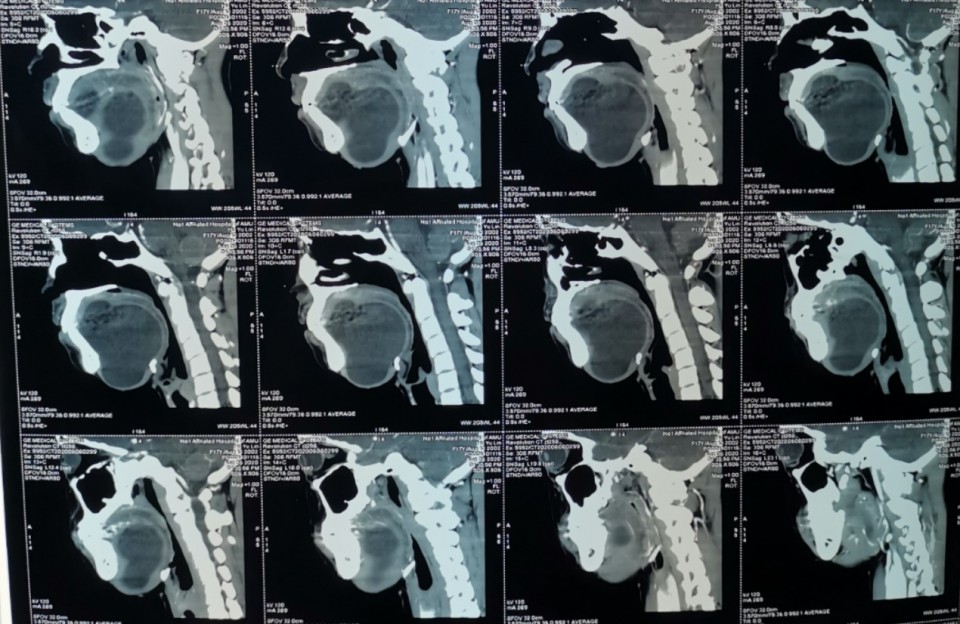

CT片可见肿物明显压迫气道